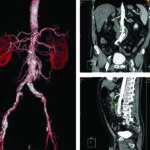

Luego de la evaluación ultrasonográfica inicial podemos optar por diferentes métodos de diagnóstico por mágenes de manera tal de ampliar el algoritmo diagnóstico y tener una visión más amplia de esta patología. La Angio TC helicoidal, con contraste, es el segundo paso y pre quirúrgico que permitirá no solo realizar una evaluación multiplanar del paciente sino también generar reconstrucciones tridimensionales y así obtener una representación más anatómica de los elementos vasculares (Fig. 31).

Este método de diagnóstico nos permite medir el aneurisma en los planos axial, coronal y sagital, evaluando su cuello y relación con las arterias renales; es indispensable para planear el tratamiento endovascular.